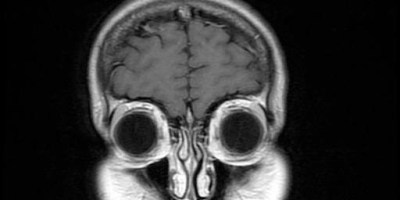

Ghosts In The MRI Machine